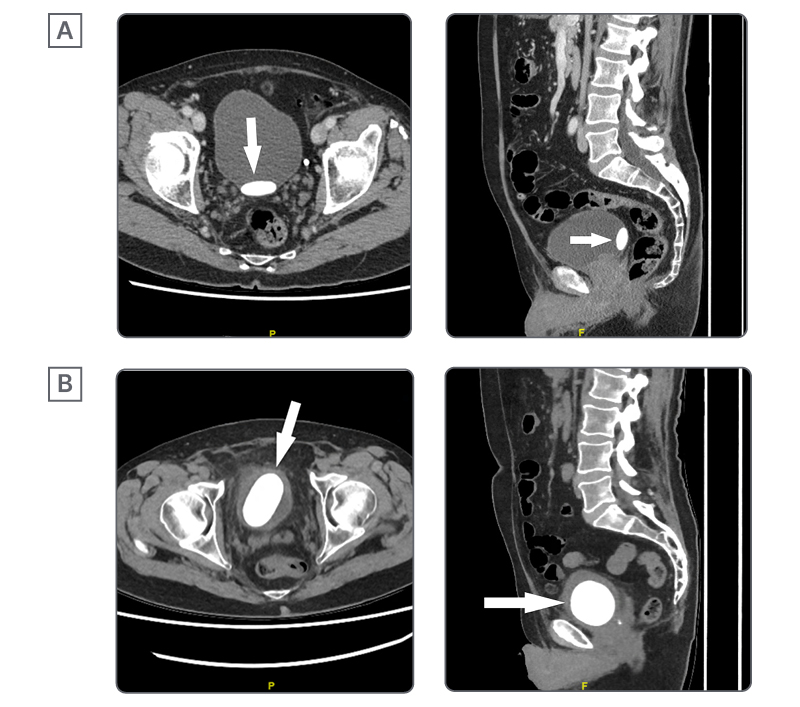

An 80-year-old healthy White man originally presented with lower abdominal pain and a 3.2 cm stone on abdominal/pelvic CT (Figure 1A). He was not interested in follow-up investigations and he declined treatment for his stone at the time of follow-up with another urologist. He was counselled at that time about the long-term risks of declining further investigations or treatment and did not book any follow-up care.

A new abdominal/pelvic CT scan showed a 6 cm bladder calculus, and mild left kidney pelviectasis (Figure 1B). A 3D CT reconstruction is shown in Figure 2. Creatinine was 138 µmol/L with a baseline of 120 µmol/L. White blood cell count was 10.9×109 /L and haemoglobin was 157 g/L. Urine culture had insignificant growth. Catheter placement with cystoscopy and guidewire failed as the balloon burst shortly after placement. On cystoscopy, the patient had evidence of a moderately obstructing prostate. There were no urethral abnormalities. The urothelium could not be visualised, as the stone was occupying the entire bladder space.

Figure 1: Axial and sagittal CT scans of bladder stone at initial presentation (A) and 32 months after initial presentation (B).